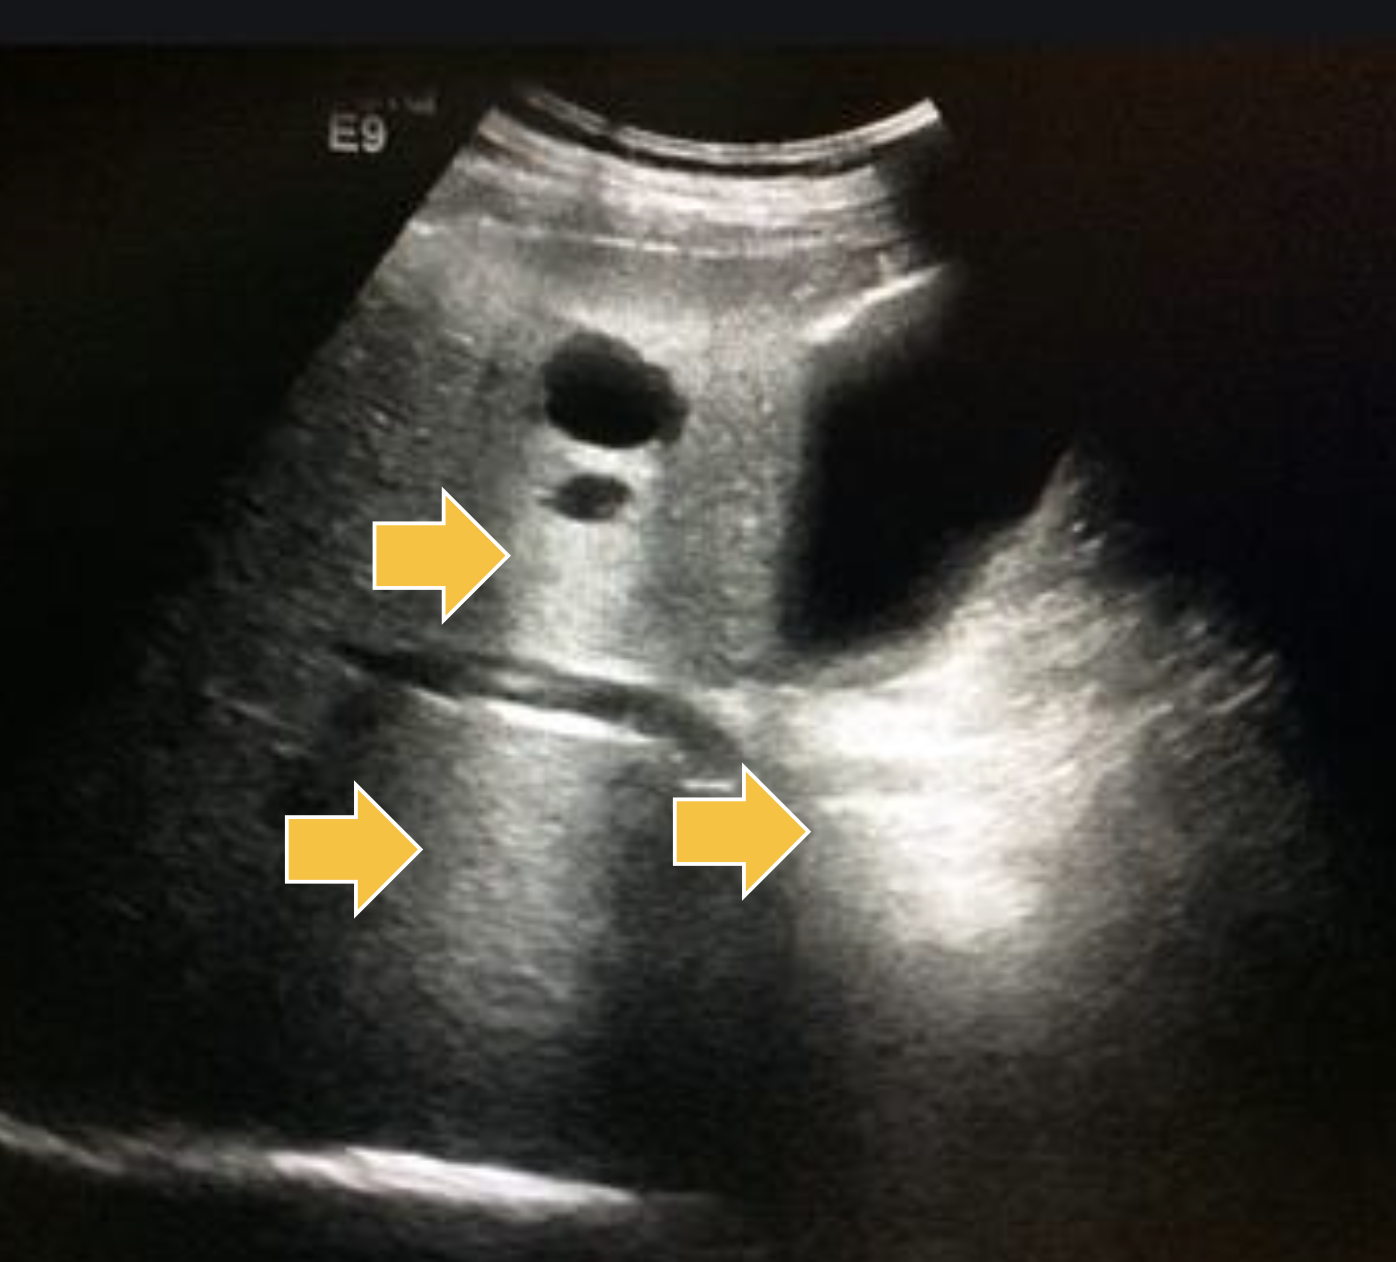

What ultrasound artifact has sound waves reflecting multiple times between strong reflectors?

Reverberation Artifact

Where is Reverberation Artifact most common?

Lungs

What ultrasound artifact causes the duplication of image of the opposite side of a strong reflector?

Mirror Image Artifact

Where is the Mirror Image Artifact most common?

What medium would be the strong reflector?

Thorax/Abdomen Interface

Diaphragm

What ultrasound artifact can be seen from imaging a 3D structure with anechoic fluid?

Slice Thickness Artifact

Where does Slice Thickness Artifact most commonly occur?

Gall Bladder and Bladder

can see artificial sludge